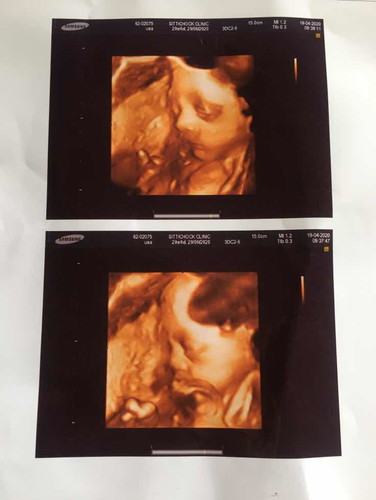

ตอนนี้29w6d หมอบอกว่าลูกหนักโล4แล้ว อยากรู้ว่าปกติมั้ยคะ หรือว่าตัวเล็กไปหรือใหญ่ไป ของแม่ๆตอน29wลูกหนักเท่าไหร่กันคะ

น้ำหนักดีอยู่นะคะ เท่ากันเลยตอนเราอายุครรภ์ 30 weeks

4โลใหญ่เลยค่ะ